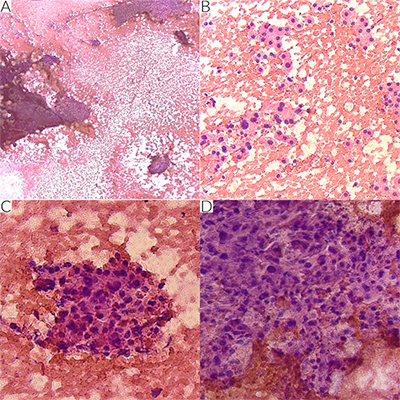

A female in her 60s with a 30-year smoking history, COPD and emphysema was found to have a 1.9 x 1.6 cm right lower lobe solitary lung nodule on CT imaging of the chest. The patient presented for a robotic navigated bronchoscopic aspiration and biopsy. Three passes were sent for intraoperative cytology adequacy and assessment. On low power, the smears showed sheets and clusters of small, bland appearing cells (Figure 1A). On higher power, loosely cohesive clusters and dispersed single cells with nuclear enlargement, hyperchromasia, and moderate cytoplasm were appreciated. Some cells showed a plasmacytoid appearance (Figure 1B-D). The differential diagnosis included typical and atypical carcinoid, granular cell tumor, plasmacytoma, and neuroendocrine carcinoma, amongst others. Given the lack of necrosis and no evident increase in mitosis, a low-grade neoplasm, favor carcinoid, defer to permanent was rendered. There was no concurrent surgical frozen.

Figure 1 Intraoperative smears stained with H&E. Sheets and clusters of fairly small, bland appearing cells x 4x (A). Cells appear loosely cohesive and as dispersed individual cells with enlarged hyperchromatic nuclei showing moderate nuclear pleomorphism. Some cells have a plasmacytoid appearance x 20x (B-D).